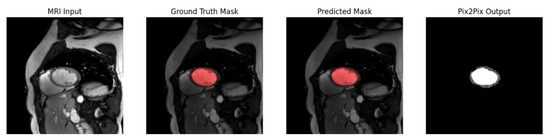

The rapid development of Generative Adversarial Networks (GANs) has transformed medical image processing, enabling realistic image synthesis, augmentation, and restoration. This study presents a comparative evaluation of three representative GAN architectures, Pix2Pix, SPADE GAN, and Wasserstein GAN (WGAN), across multiple medical imaging tasks,

The rapid development of Generative Adversarial Networks (GANs) has transformed medical image processing, enabling realistic image synthesis, augmentation, and restoration. This study presents a comparative evaluation of three representative GAN architectures, Pix2Pix, SPADE GAN, and Wasserstein GAN (WGAN), across multiple medical imaging tasks, including segmentation, image synthesis, and enhancement. Experiments were conducted on three benchmark datasets: ACDC (cardiac MRI), Brain Tumor MRI, and CHAOS (abdominal MRI). Model performance was assessed using Fréchet Inception Distance (FID), Peak Signal-to-Noise Ratio (PSNR), Structural Similarity Index (SSIM), Dice coefficient, and segmentation accuracy. Results show that SPADE-inpainting achieved the best image fidelity (PSNR ≈ 36 dB, SSIM > 0.97, Dice ≈ 0.94, FID < 0.01), while Pix2Pix delivered the highest segmentation accuracy (Dice ≈ 0.90 on ACDC). WGAN provided stable enhancement and strong visual sharpness on smaller datasets such as Brain Tumor MRI. The findings confirm that no single GAN architecture universally excels across all tasks; performance depends on data complexity and task objectives. Overall, GANs demonstrate strong potential for medical image augmentation and synthesis, though their clinical utility remains dependent on anatomical fidelity and dataset diversity.